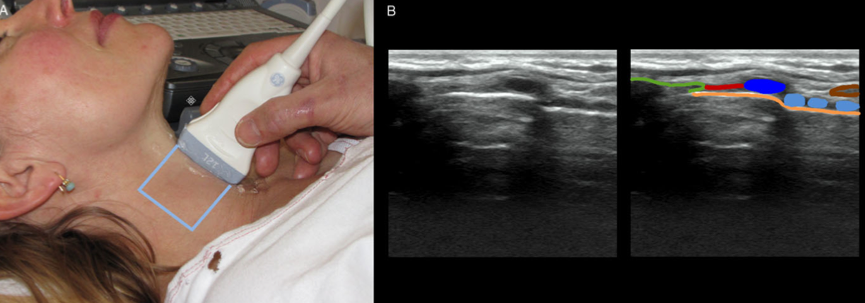

Os dejamos enlace al articulo de revisión del uso de Ecografia en VA publicado en el Acta Anaesthesiologica Scandinavica. M.S.Kristensen. Acta Anaesthesiol Scand 2011;55:1155-1173